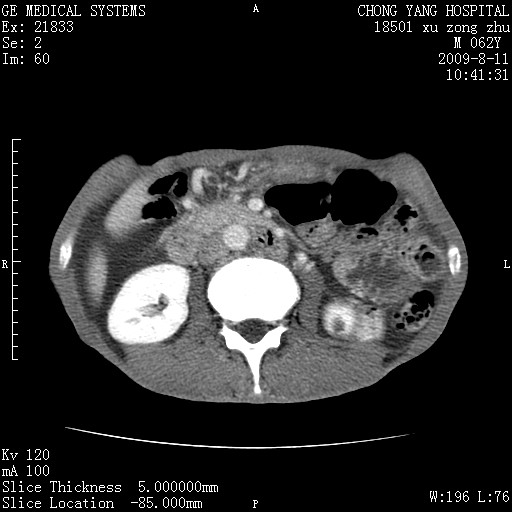

以下是引用杀毒软件在2009-8-11 16:35:00的发言:[br]肝内胆管扩张局限于左叶,胆管内有结石伴肝外胆管结石,胆管壁增厚呈弥漫性并发腹腔积液,胰腺边界模糊。[br][br]考虑---胆总管及肝内胆管结石继发胆管炎及胰腺炎,左肾下极囊肿,腹水。

以下是引用zjzjr在2009-8-11 17:35:00的发言:[br]肝内胆管扩张局限于左叶,胆管内有结石伴肝外胆管结石,胆管壁增厚呈弥漫性并发腹腔积液。[br][br]考虑---胆总管及肝内胆管结石继发胆管炎,左肾下极囊肿,腹水。